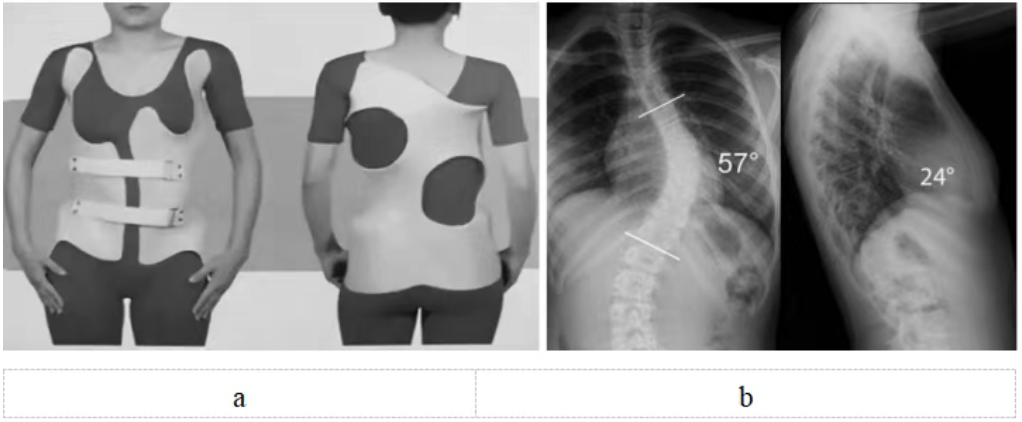

脊柱側彎支具治療需專業(yè)定制(圖5),日用型每天佩戴20小時以上,夜用型需整晚佩戴。初期可能有不適,需1~2周適應期,要注意皮膚護理。必須堅持佩戴至骨骼發(fā)育成熟,通常需要2~3年。矯正效果取決于佩戴時長和持續(xù)性,家長要做好監(jiān)督。

圖5 a:特發(fā)性脊柱側彎(中度)配戴支具正面觀和背面觀;b:特發(fā)性脊柱側彎(重度)X線正側位,需要手術治療。注:a和b非同一患者

重度側彎(Cobb角>40度)(圖5):